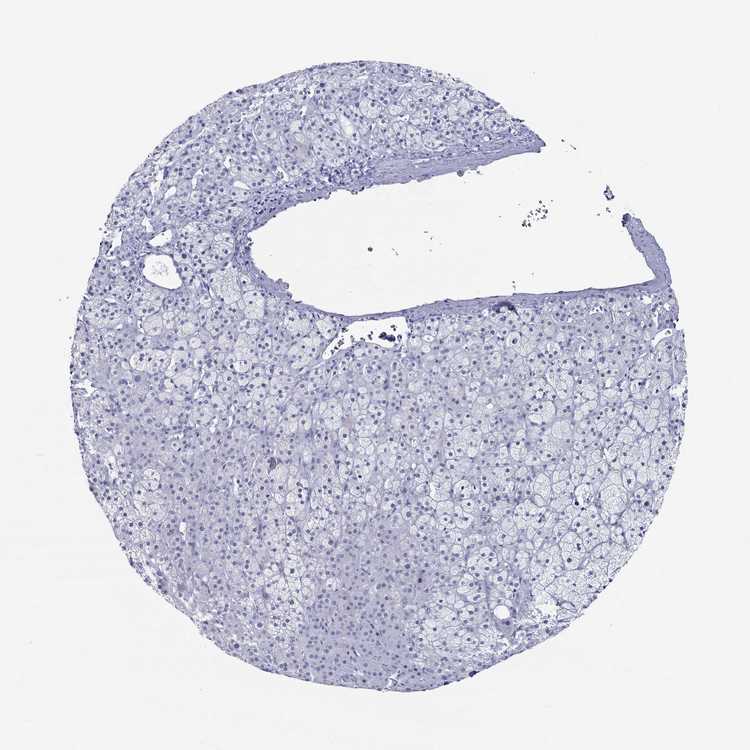

ADRENAL GLAND - Antibody stainingi

Antibody staining in the annotated cell types in the current human tissue is reported as not detected, low, medium, or high, based on conventional immunohistochemistry profiling in selected tissues. This score is based on the combination of the staining intensity and fraction of stained cells.

Each image is clickable and will lead to virtual microscopy that enables deeper exploration of all samples and also displays staining intensity scores, fraction scores and subcellular localization as well as patient and tissue information for each sample.

Antibody HPA077485

Glandular cells Not detected